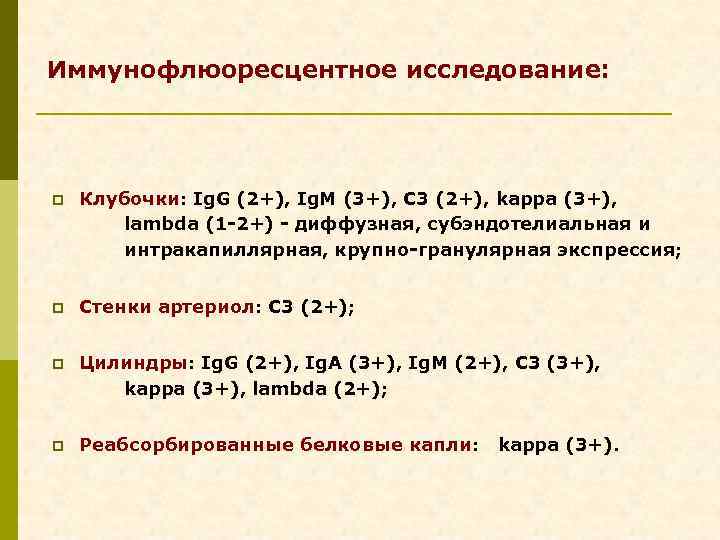

Иммунофлюоресцентное исследование: p Клубочки: Ig. G (2+), Ig. M (3+), C 3 (2+), kappa (3+), lambda (1 -2+) - диффузная, субэндотелиальная и интракапиллярная, крупно-гранулярная экспрессия; p Стенки артериол: C 3 (2+); p Цилиндры: Ig. G (2+), Ig. A (3+), Ig. M (2+), C 3 (3+), kappa (3+), lambda (2+); p Реабсорбированные белковые капли: kappa (3+).

Предварительное гистологическое заключение: p Мембрано-пролиферативный, HCV-ассоциированный, криоглобулинемический(? ) гломерулонефрит с полным склерозом 47% клубочков, сегментарным склерозом 22% клубочков и формированием полулуний в 15% клубочков; p диффузно-очаговый выраженный острый канальцевый некроз; p выраженный артерио-артериолосклероз. Примечание: Криоглобулинемическая природа поражения будет уточняться при ЭМ-исследовании.

Заключение p Мембрано-пролиферативный гломерулонефрит, криоглобулинемический, ВИЧ-ассоциированный, на фоне гепатита С